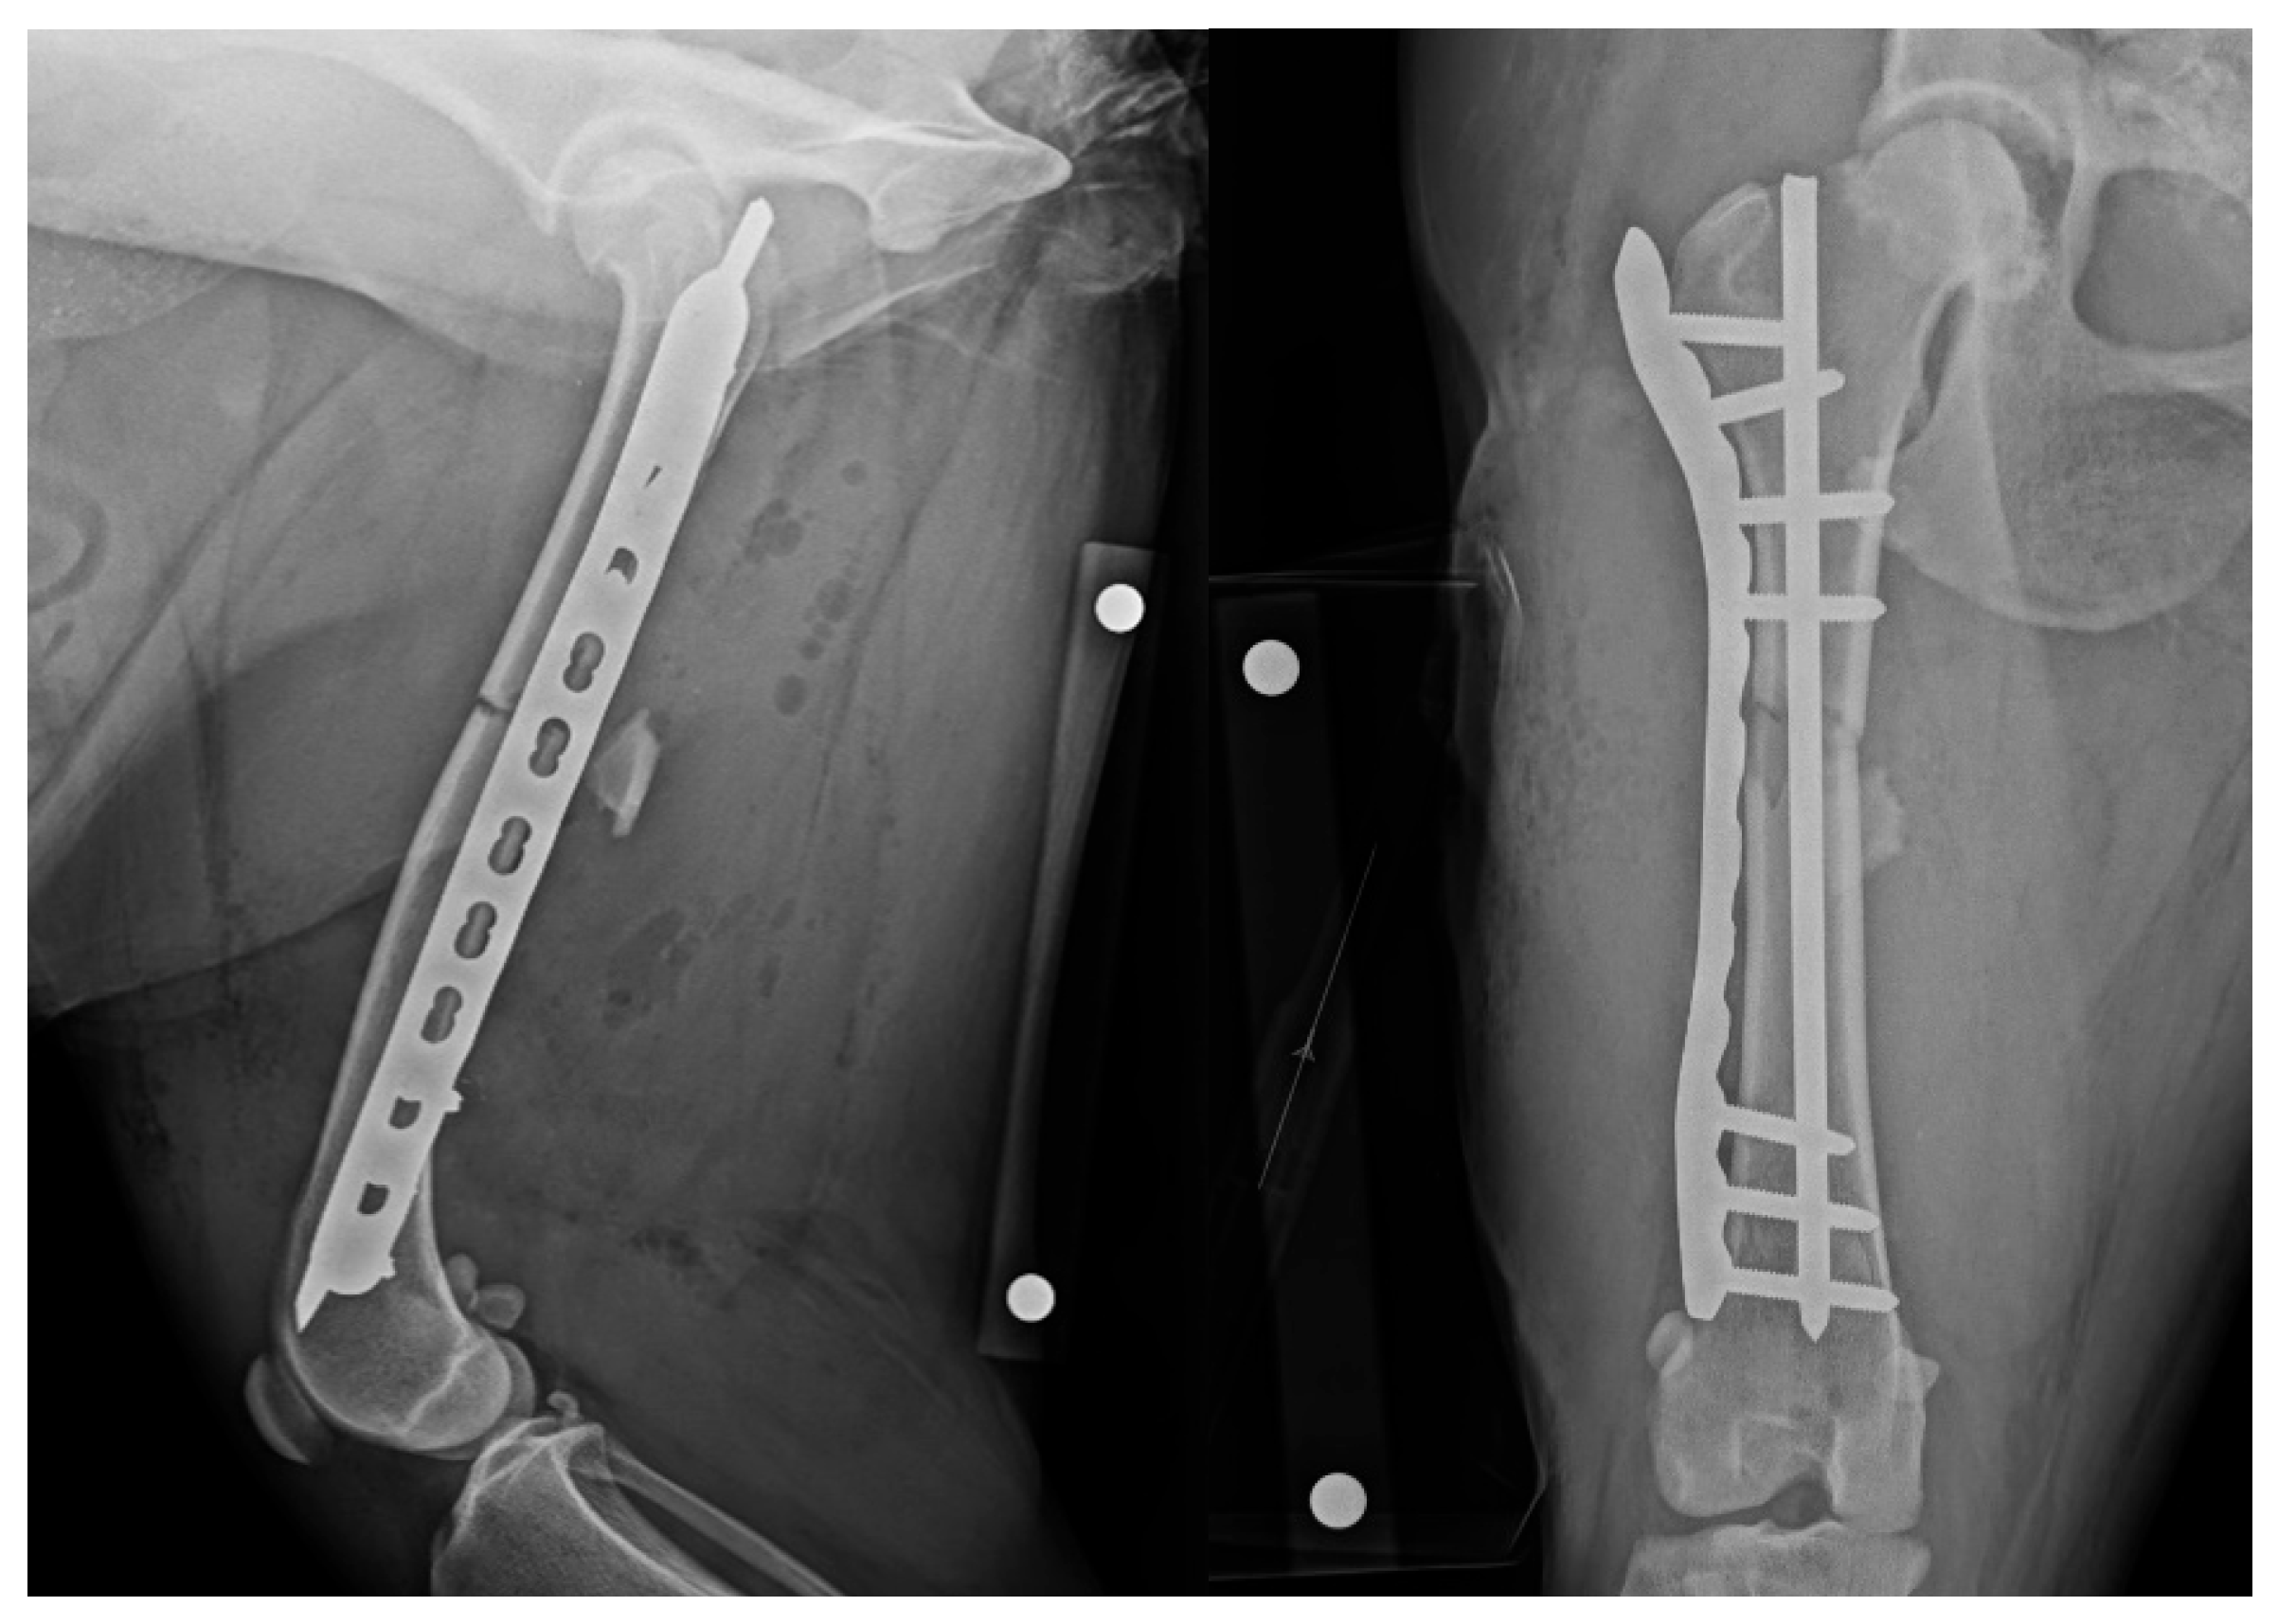

2.4. Post-Operative Imaging

2.5. Revision

2.6. Post-Operative Management